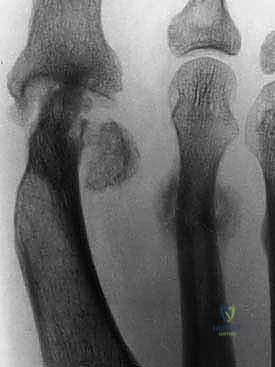

6. التثبيت الداخلي الصلب (Rigid Internal Fixation)

لضمان التئام العظام (وهو ما يستغرق عدة أسابيع)، يجب تثبيت المفصل والطعم العظمي بقوة شديدة. يستخدم الأستاذ الدكتور محمد هطيف أحدث الشرائح المعدنية المصممة خصيصاً لاندماج إبهام القدم (Anatomical Locking Plates) والمسامير التيتانيوم. يتم وضع الشريحة فوق المفصل وتثبيتها بمسامير تمر عبر الطعم العظمي لضمان ثباته المطلق.

7. الإغلاق والتحقق بالأشعة

يتم أخذ صور أشعة سينية داخل غرفة العمليات (Fluoroscopy) للتأكد من المحاذاة المثالية للإصبع، وتصحيح زاوية الارتفاع، والموضع الدقيق للمسامير. بعد ذلك، يتم إغلاق الجرح بخيوط تجميلية ووضع ضمادات معقمة وجبيرة واقية.